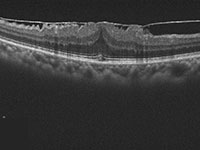

パキコロイド新生血管症(PNV)に対するマイクロパルス閾値下レーザー治療を行い、網膜下液が吸収された症例。

このように膜に個人差があり、手術のタイミングを決定することは、困難ですが、一般に自覚症状に乏しく視力が良好な時期は経過観察します。手術を検討するタイミングとしては、視力低下が進行した場合、ゆがみがひどくなった場合、運転などの生活に支障を来した時点です。OCTという網膜の断層撮影を定期的に行ってゆくと、網膜の外層という視細胞が集まっている層に乱れを生じてくることがあり、この所見が手術の時期を決定するのに参考になります。白内障と異なり、視力が極端に低下したり、ゆがみが極端にひどくなってから手術をしても、視機能の改善には限界があり、重症の黄斑上膜を長期間放置することは望ましいことではありません。当院の大越医師は硝子体手術のエキスパートで黄斑上膜の硝子体手術を多数行ってまいりました。手術は局所麻酔にて30から40分程度で終わります。手術は聖路加国際病院で行っております。黄斑上膜の手術を受けるかどうかお悩みの方は、お気軽にご相談ください。